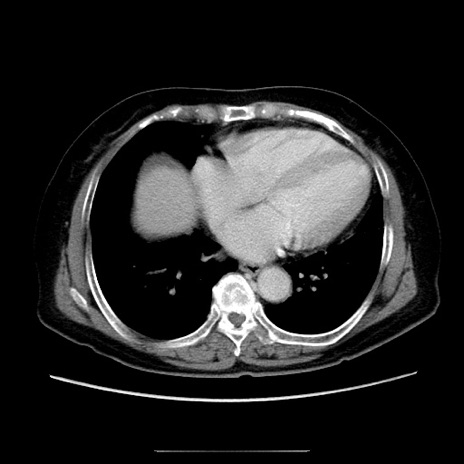

冠状断像

【症例】70歳代女性

【主訴】お腹が張る

【現病歴】1週間くらい前から腹部膨満の自覚あり。昨日夜から増悪したため、本日救急外来受診。

【身体所見】意識清明、BT 36.5℃、BP 165/106mmHg、HR 80bpm、SpO2 98%、腹部:膨満、軟、自発痛・圧痛なし、触診にて不快感あり、腸蠕動音:減弱

【データ】WBC 12600、CRP 1.04